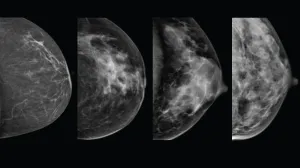

Dense Breasts + Breast Cancer Screening: What to Know

If you’re one of the more than half of women over 40 who’ve been told they have dense breast tissue, you’re not alone, and it’s natural to wonder what that means for your breast cancer risk and your screening. Radiologist Rachel Hitt, MD, MPH, Chief of Breast Imaging at Tufts Medical Center, explains what dense breast tissue is, how it can affect mammograms and the steps you can take to stay proactive about your breast health.